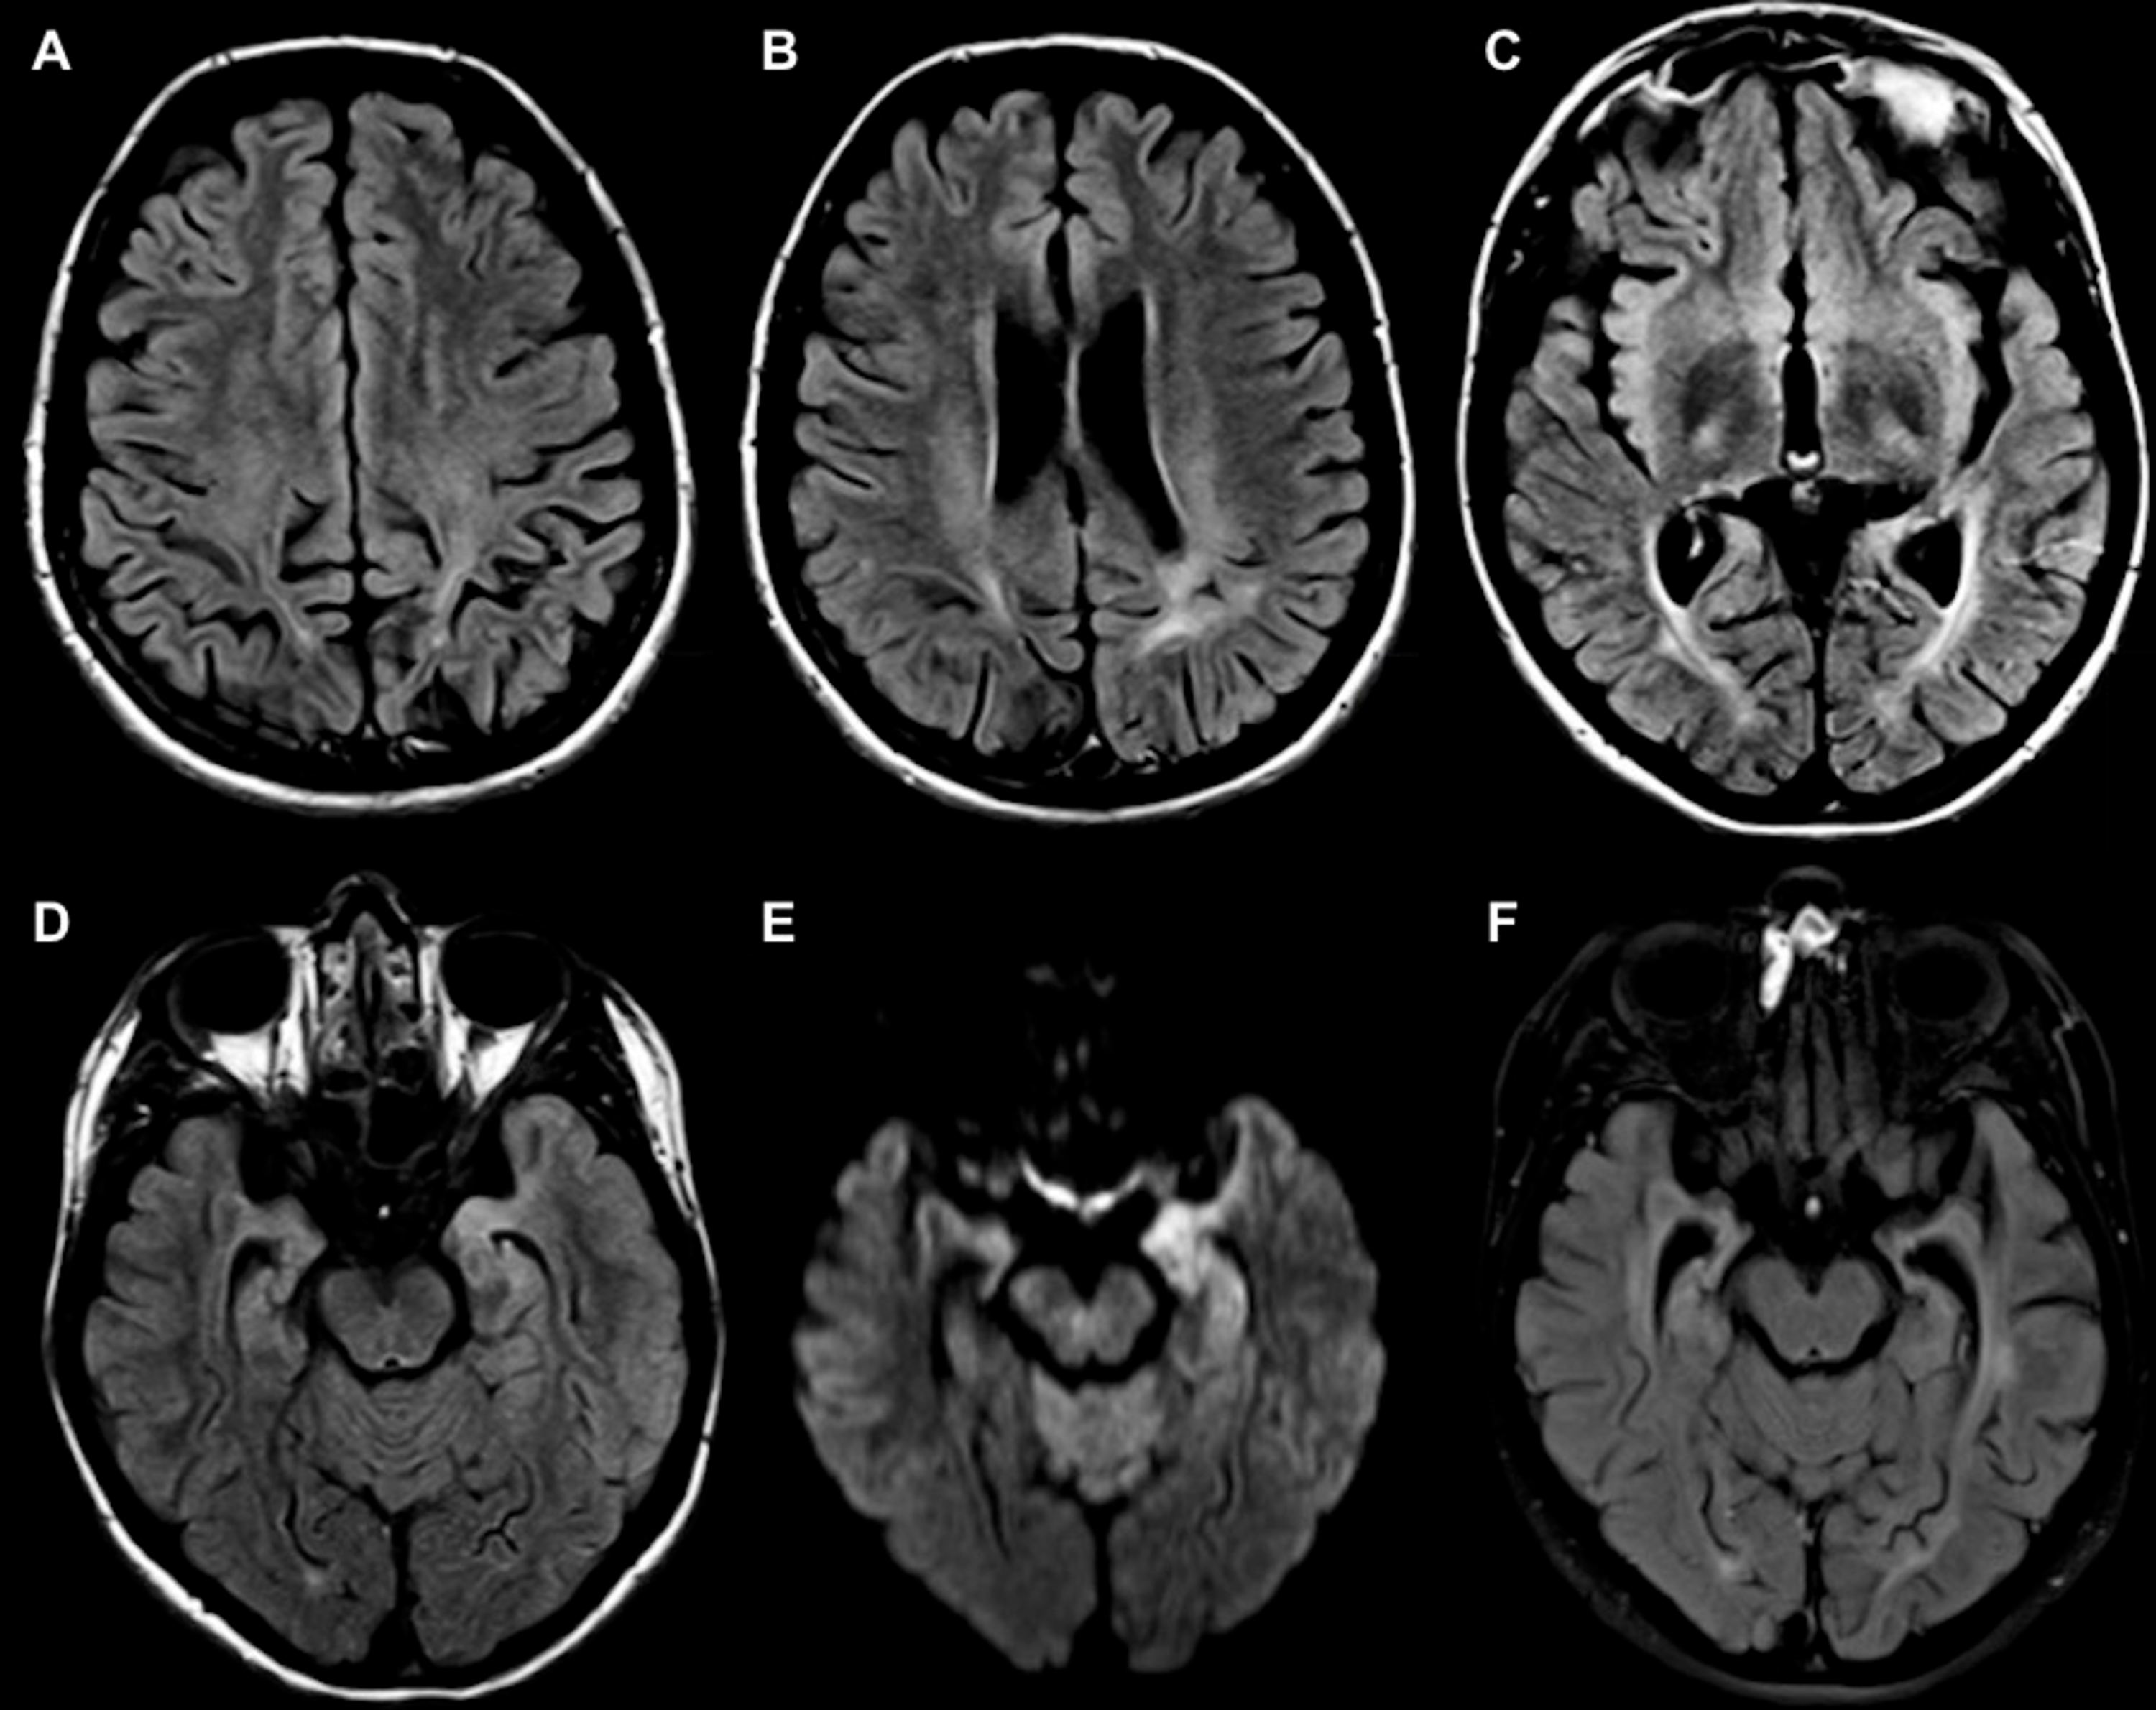

From www.cureus.com

MRI Findings and Topographic Distribution of Lesions in Metronidazole Lead Encephalopathy Radiology Lead encephalopathy is almost always associated. Lead poisoning is a common occupational health hazard in developing countries. The differential diagnosis of patients presenting with acute encephalopathy is broad. Recognizing the common imaging patterns of toxic and metabolic brain disorders can help radiologists narrow the differential. Encephalopathy is an uncommon but serious presentation of lead toxicity. Lead poisoning affects multiple organs:. Lead Encephalopathy Radiology.